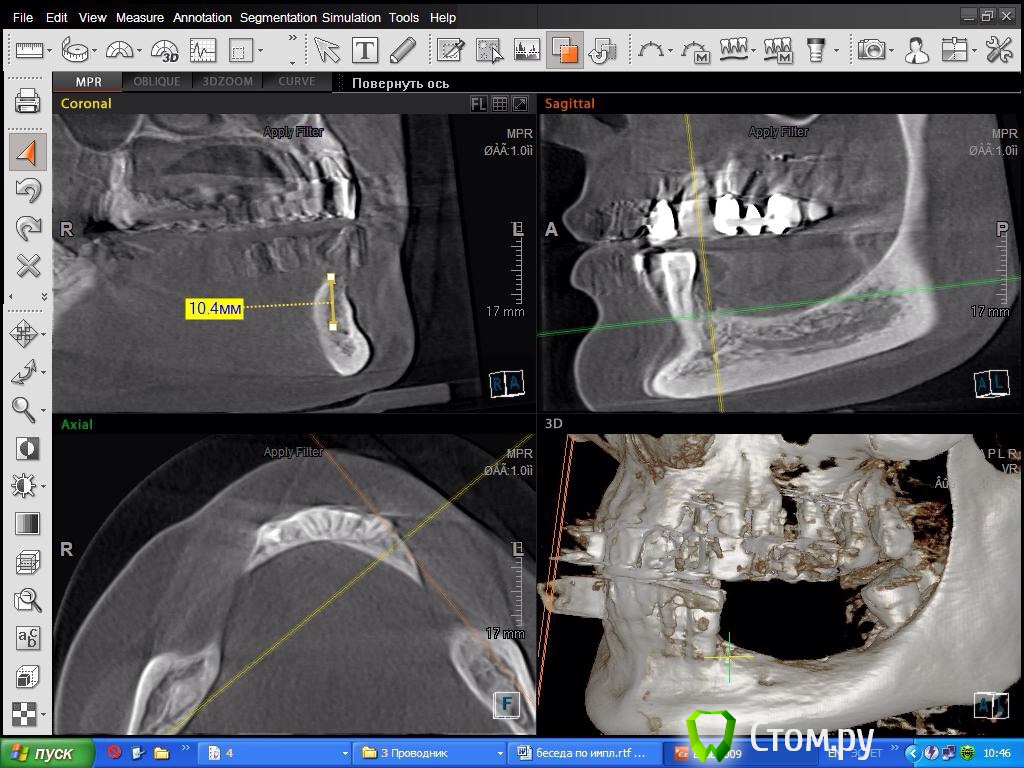

SDC Опубликовано 8 октября, 2014 Поделиться Опубликовано 8 октября, 2014 Склоняюсь в 4 кв делать консоль! Спасибо за мнениеПосмотрим срезы на уровне 2 премоляра? Получится ли имплантировать в этом месте? Ссылка на комментарий

DoktorDre Опубликовано 8 октября, 2014 Автор Поделиться Опубликовано 8 октября, 2014 Посмотрим срезы на уровне 2 премоляра? Получится ли имплантировать в этом месте?Получится, после ламинатов) Ссылка на комментарий